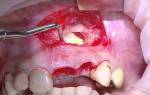

После обнаружения симптомов кисты в десне зуба, пациенту рекомендуется незамедлительно обратиться к хирургу-стоматологу. Существуют различные методы лечения кисты в ротовой полости: консервативные, оперативные и домашние (использование народной медицины). Консервативное лечение эффективно на ранних стадиях образования гнойного мешка, когда его диаметр не превышает 0,8 см и на корневые каналы не наложены пломбы. Оно включает предварительную обработку воспаленной области антисептиками и заживляющими растворами, очищение полости от жидкости, очищение поверхности зуба и установку качественной пломбы. Оперативное лечение чаще всего применяется в запущенных случаях, когда диаметр образования превышает 0,8 см, в канале корня размещен штифт, имеется коронка или 70% длины каналов запломбированы стоматологическим материалом. Ранее удаление гранулемы было связано с ампутацией воспаленного зуба, но современная медицина стремится сохранить зубы, и ампутация происходит только в редких случаях, когда корни зуба разрушены. Лазерное лечение является современным подходом для устранения кисты зуба, обеспечивая безболезненное и быстрое иссечение гнойного мешка и минимизируя риск инфекции и осложнений. Однако не все стоматологии оснащены лазерными аппаратами, поэтому существуют классические методы проведения процедуры: цистостомия, гемисекция и цистэктомия. После хирургического вмешательства пациенту рекомендуется принимать обезболивающие препараты и полоскать рот антисептическими препаратами, травяными и лечебными настоями. Отек и покраснение обычно проходят через 4-5 суток.